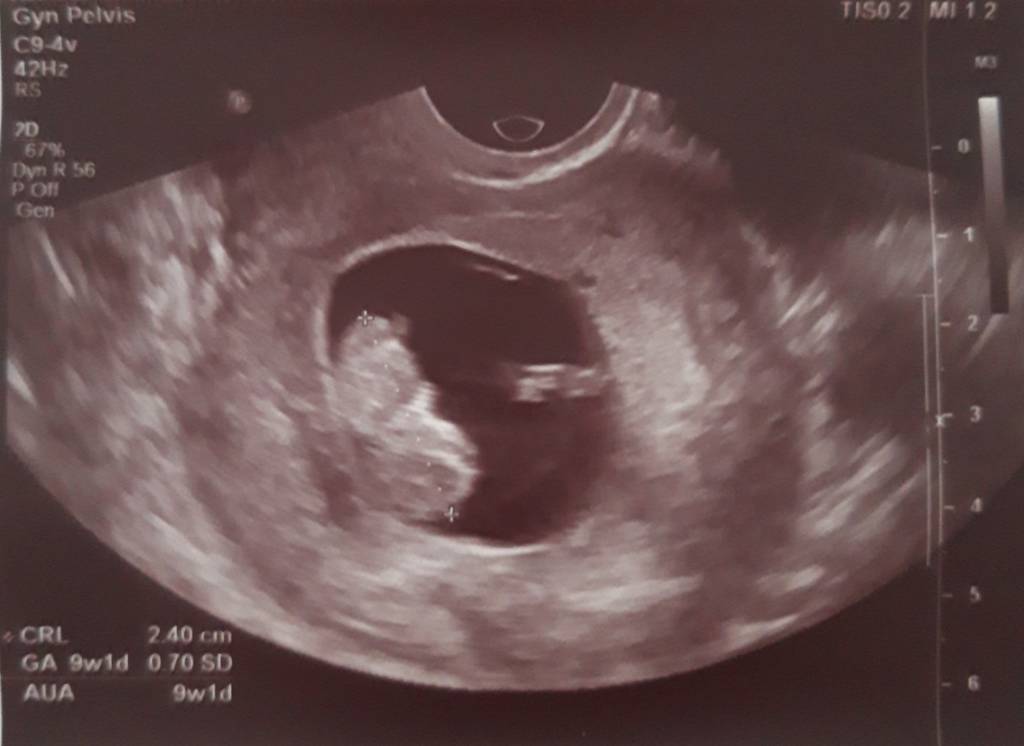

Wczoraj miałam wizytę u gina termin om zgodny z usg na 20.06.[emoji3] Dzidzia ma 2.40 cm serduszko bije 174bmp.[emoji7]

Ale glukoza wyszła mi za dużo bo aż 106 [emoji853]zakaz jedzenia słodyczy owoców, soków masakra tych słodyczy to mogę nie jeść i tak nie jem ale nie wiem jak sobie poradzę bez owocy[emoji37][emoji37] w tygodniu powtarzam glukozę i zobaczę co wyjdzie. Oto moja kruszynka.[emoji7][emoji7][emoji7]